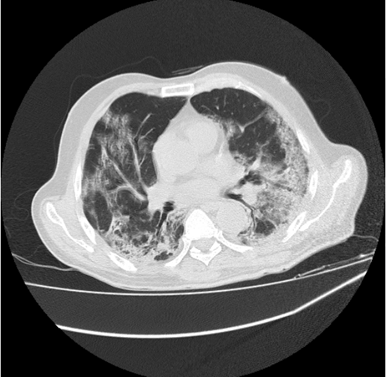

In most of the patients with COVID pneumonia, the tomographic findings show ground-glass opacity (GGO). In almost all the CT images of COVID patients, the GGO is prominent, which reflects that it is almost present in all samples and thus reflects the presence of COVID, and probability reflects the early stage. (Figure 2)

Figure 2 Spatial Thickness found in CT Image 2.

The image reflects the Covid pulmonary consolidation which tends to be patchy or segmental and nodular. It reflects the sensitive stage of the patient, especially when around 10-12 days have passed. Initially, the appearance of GGO reflects early stage of COVID, but as it develops, it continues increasing pulmonary consolidation and air bronchogram in lungs. (Figure 3)

Figure 3 CT image reflecting COVID pulmonary consolidation.